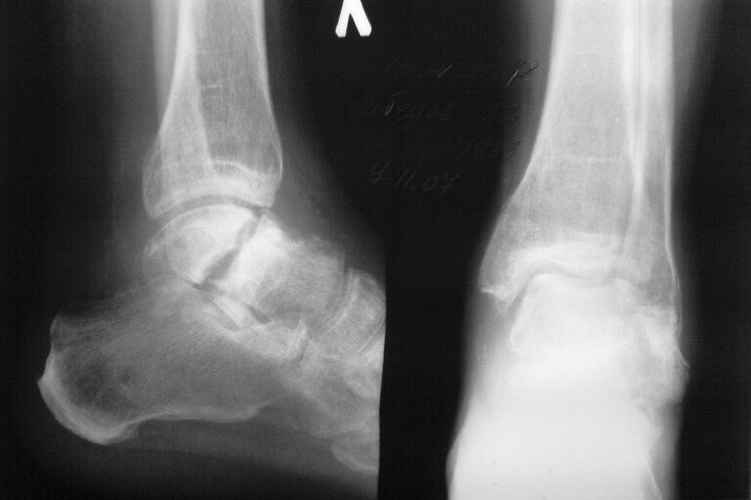

Its a grave picture.

I doubt whether 2 stages- reduction and fusion followed by a prosthesis+ subtalar fusion would be better-a pantalar fusion or talectomy would be the best-depending on soft tissue stage and vascularity of the talus and general health

снимки конечно совсем не ах!!но и на них видно что имеет место быть ас. некроз тарана, лечение микродистракцией в КДА очень сомнительное, наиболее быстрый и функциональный результат будет достигнут путем артродеза. А вам необходимо просто правильно побеседовать с пациентом, а он должен "созреть" на операцию.

Магниторезонансная томогорафия более информативна для остеонекроза тарана.

На ренгенограмме между передней и задней частями

тарана нет большой разницы костных структур,

сохранный таранный купол и имеется склероз на месте несращения. Трудно угадать дальнейший процесс, но я бы остановился на подтаранном артродезе с фиксацией перелома. Таким образом, можно сохранить опороспособность и движения в голеностопе.